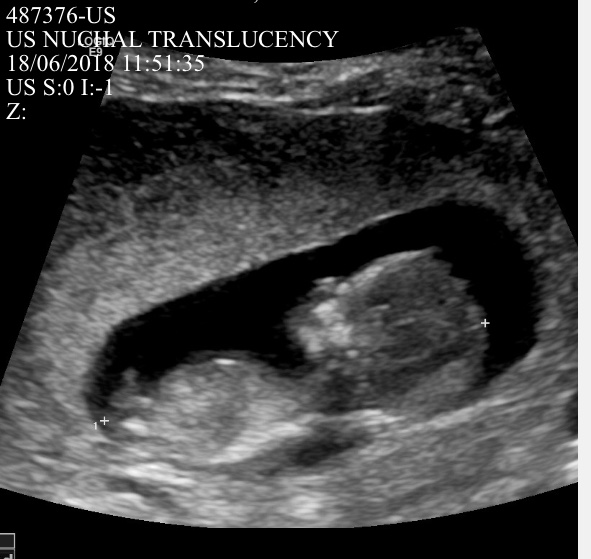

Hi guys. I’m posting 2 profile photos and 2 potty shots from my 12 week scan (measure 12w1d). I am not sure if either of the profile photos show a nub - if so, what are your guesses based on either of the profile photos or the potty shot?

I see 3 lines in the potty shot but the middle line is much longer pointing out. I will update on Friday when I find out but would love some guesses until then. TIA. Attachment 39791Attachment 39792Attachment 39793Attachment 39794